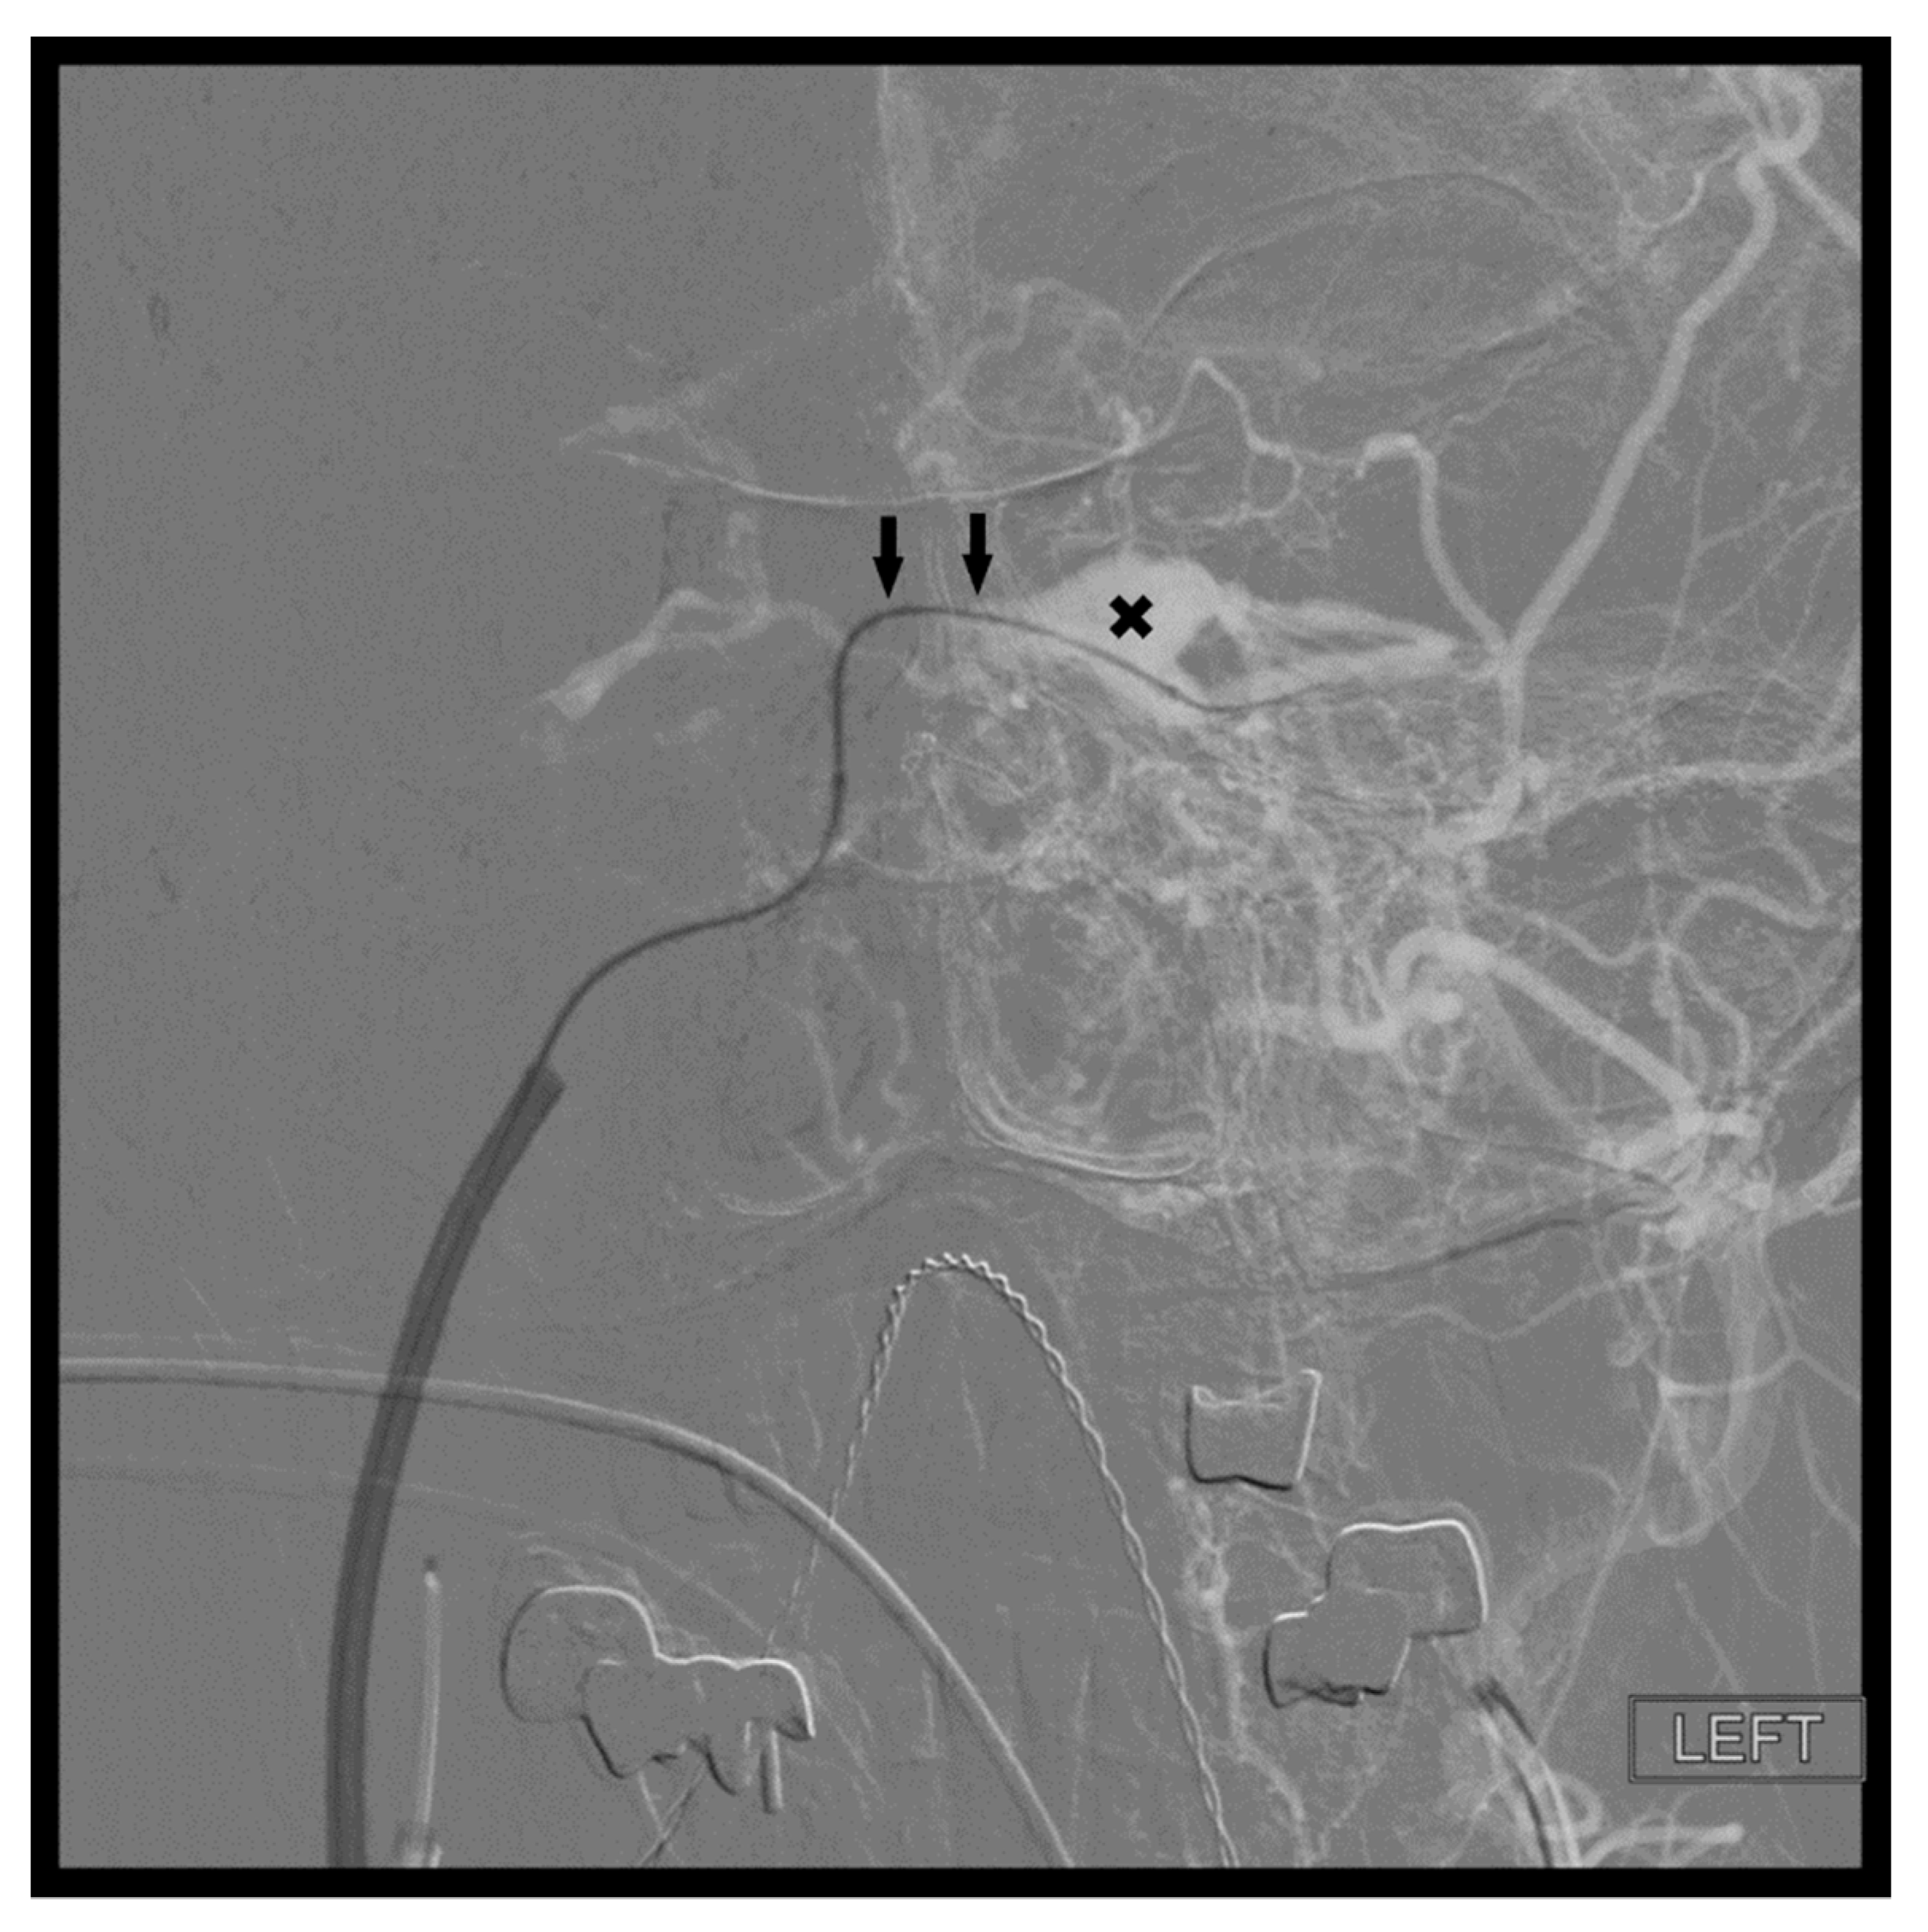

Figure 1. The common facial vein (CVF), anterior facial vein (AFV), angular vein (AV), retromandibular vein (RMV), middle temporal vein (MTV), superficial temporal vein (STV), and cavernous sinus (X) are demonstrated.

Figure 6. Demonstrates access of the left cavernous sinus (X) through an intercavernous approach (arrows).